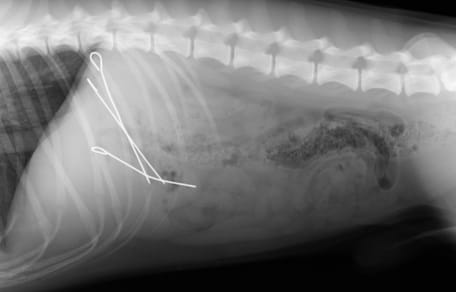

Le contrat santé va ainsi prendre en charge les consultations, les soins vétérinaires, les examens réalisés, les frais d’hospitalisation, les interventions chirurgicales, les achats de médicaments ou encore le décès de l’animal.